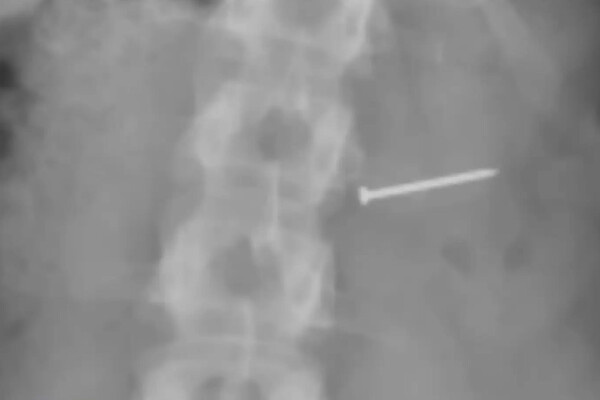

Инцидент произошел 11 сентября 2018 года — женщина купила порцию мороженого со вкусом сливочного ореха пекан в автокассе сети Bruster's Ice Cream в городе Палм-Бей. Откусив кусочек, она почувствовала, что в горле что-то застряло. Позже в больнице выяснилось, что она проглотила металлический гвоздь. Как утверждается в иске, в десерте оказались не только гвозди, но и металлические осколки.

В результате женщина получила серьезные и необратимые травмы головы, шеи, конечностей и нервной системы, а также значительные шрамы. Кроме того, она лишилась возможности иметь детей. Пострадавшая с мужем заявили, что инцидент помешал им расширить семью. Кроме того, женщина накопила огромные медицинские счета и потеряла доход.